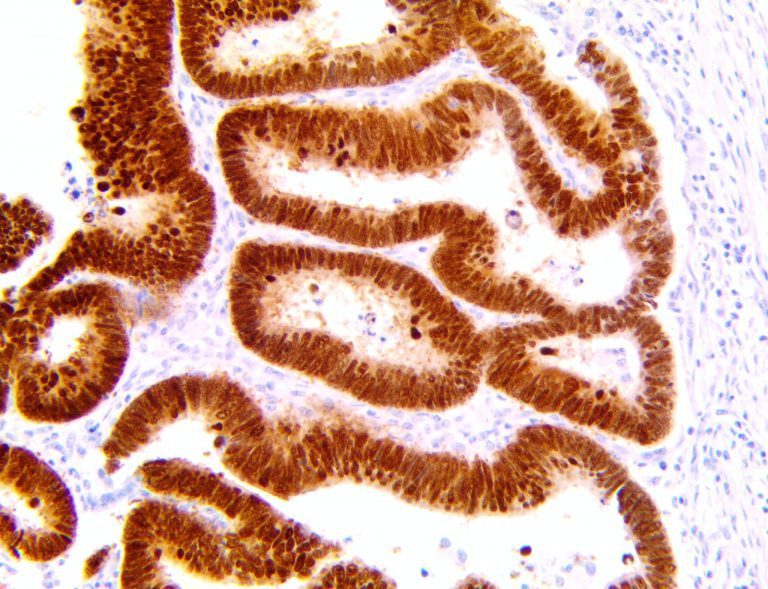

The first cytokines released are interleukin 1β (IL-1β) and tumor necrosis factor-α (TNF-α), which attract a variety of circulating white blood cells (WBCs) to the infection site, including neutrophils, monocytes, macrophages, and natural killer (NK) cells. This response, along with the antipathogenic chemicals released by these cells (i.e., complement), comprise the innate immune response. These cells directly attack the invading pathogen and also release additional cytokines, chief among them interleukin-1 and 6 (IL-6). IL-6 is essential for invoking the adaptive immune response, which calls T-cells, B-cells, and T helper (Th) cells to the infection site. IL-6 also stimulates further recruitment, proliferation and activation of macrophages.

This activation induces inflammatory monocytes to highly express IL-6, starting a localized and then systemic cascade effect that results in hyperproduction of IL-6, which accelerates the inflammatory process. Because IL-6 also increases vascular permeability, excessive levels cause blood vessels to become very leaky. This, along with clotting factors released from vascular endothelial cells, stimulates the coagulation cascade, resulting in microthrombosis (tiny clots), which leads to ischemia and tissue death of the kidney, intestines, heart, liver, brain and extremities.